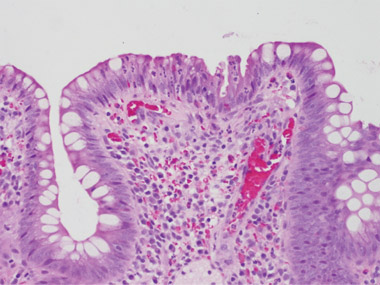

On her arrival back in Australia, the symptoms recurred. An ileoscopy on 4 February 2009 showed a single inflamed ulcerated area close to the stoma, and biopsy specimens of this area were reported as consistent with pseudomembranous enteritis and C. difficile infection (Box 1). Culture of the ileostomy fluid again resulted in the isolation of toxigenic C. difficile.

We are grateful to Professor Vincent Caruso (St John of God Hospital Pathology, Western Australia) for providing the photomicrographs.